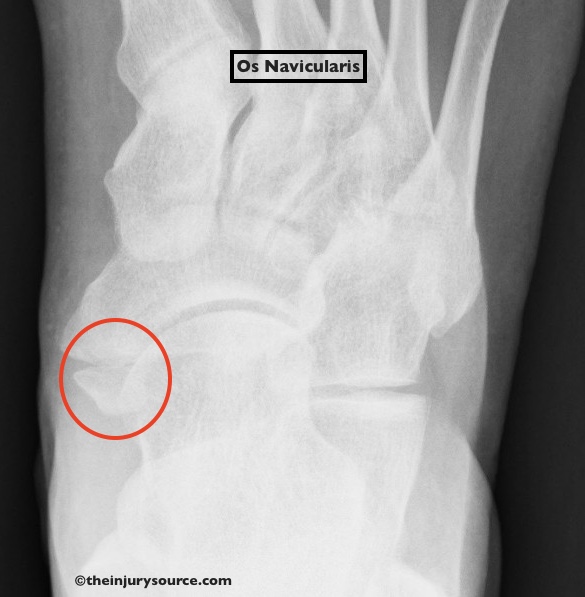

Os naviculare перевод

Os naviculare перевод 144 фотографий